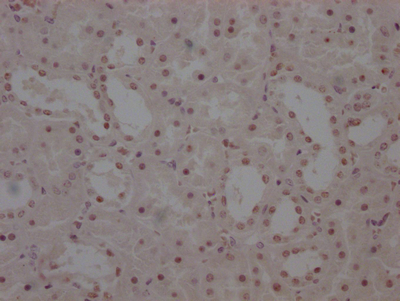

圖片: